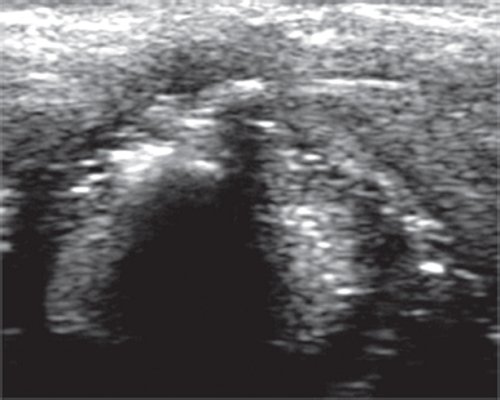

В норме при УЗИ хрящи и мягкие ткани гортани расположены симметрично, аваскулярны (рис. 2, а). В режиме серой шкалы можно наблюдать, как голосовые складки расходятся на вдохе и сближаются на выдохе, внутренний контур их гипоэхогенный и нечеткий, так что оценить степень смыкания по аналогии с эндоскопией гортани (рис. 2, б) по УЗИ невозможно. Визуализация мелких краевых образований на голосовых складках также крайне затруднительна.

а) УЗИ гортани в режиме серой шкалы. Поперечный срез на уровне голосовых складок.